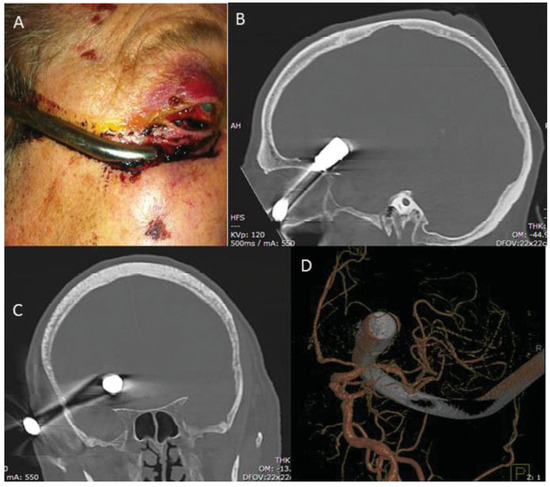

Extraction of Fronto-Orbital Shower Hook Through Transcranial Orbitotomy

:Case Report